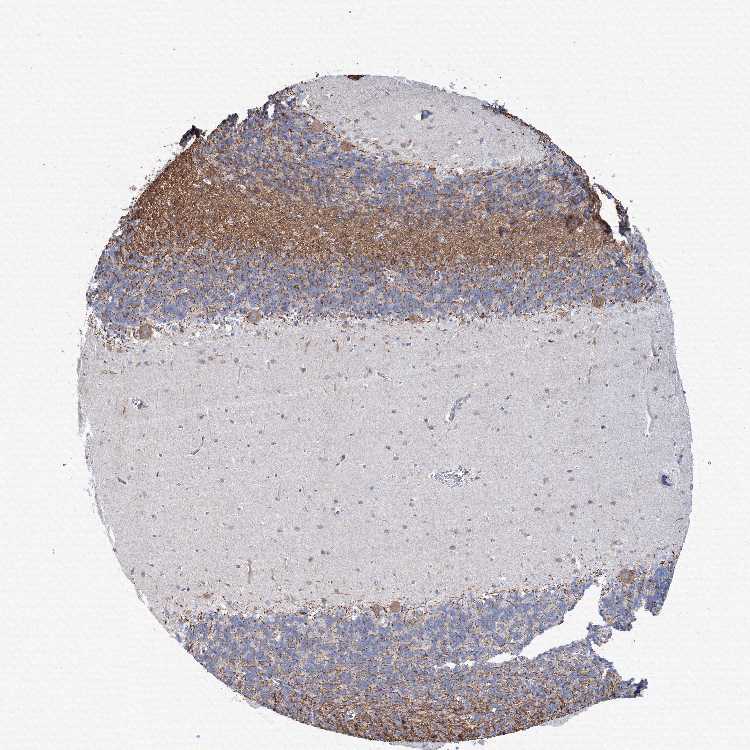

BRAIN CEREBELLUM Show tissue menu

CEREBELLUM - Expression summary

CEREBELLUM - Antibody stainingi

Antibody staining in the annotated cell types in the current human tissue is reported as not detected, low, medium, or high, based on conventional immunohistochemistry profiling in selected tissues. This score is based on the combination of the staining intensity and fraction of stained cells.

Each image is clickable and will lead to virtual microscopy that enables deeper exploration of all samples and also displays staining intensity scores, fraction scores and subcellular localization as well as patient and tissue information for each sample.

Antibody HPA036750

Purkinje cells Medium

Cells in granular layer Not detected

Cells in molecular layer Low